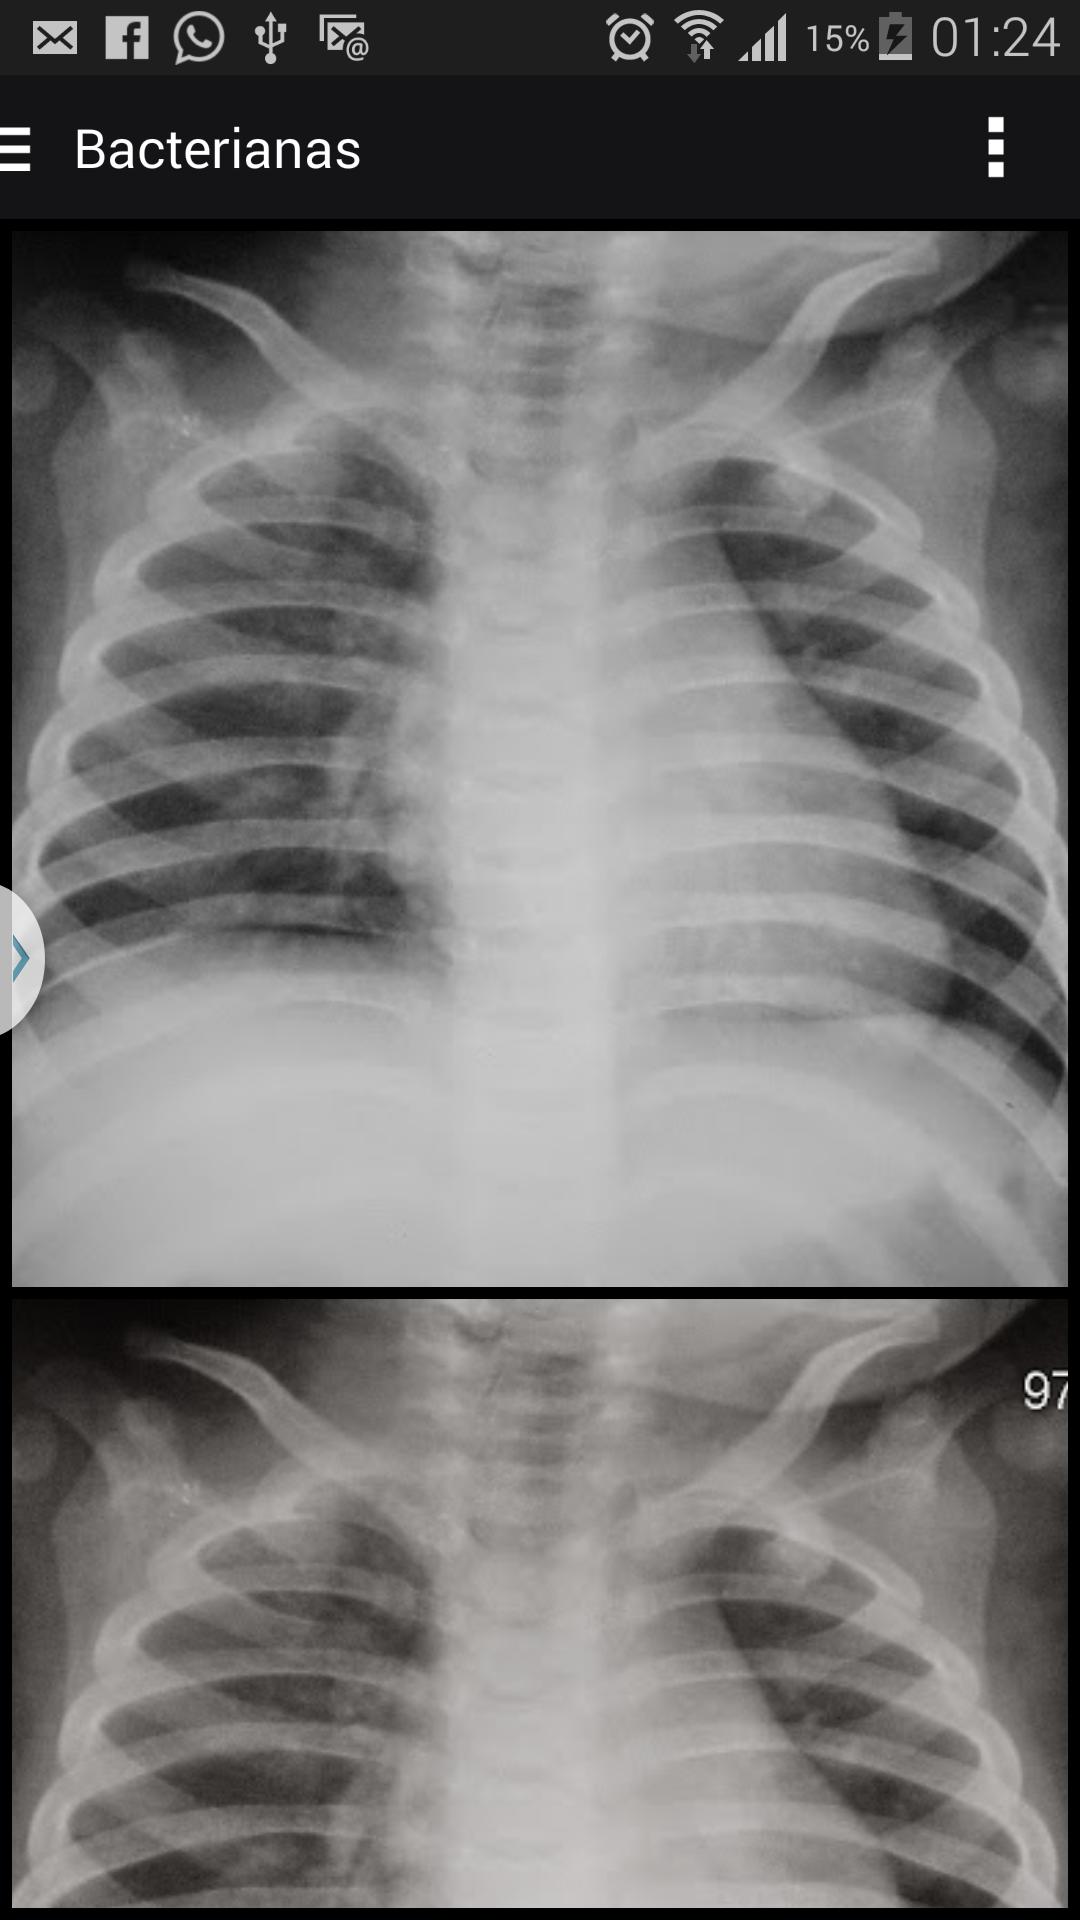

صور الأشعة السينية لدعم تشخيص الالتهاب الرئوي عند الأطفال

تعتبر منظمة الصحة العالمية من قبل منظمة الصحة العالمية (WHO) أفضل طريقة متاحة حاليًا لتشخيص الالتهاب الرئوي في الممارسة السريرية اليومية. تعتبر الدراسات التي أجريت على تباين interobserving شائعًا في جميع مجالات الطب ، ومع ذلك ، تسود في دراسات الصور ، بالنظر إلى أنه في هذا المجال ، يمثل أداء المراقب الجزء الهش ، يتناقض مع التقدم التكنولوجي ، الذي تم الحصول عليه في العقد الماضي.

الذهب "العامل الأساسي في تقييم الاختبارات التشخيصية. في حالة التشخيص الشعاعي للصدر ، وخاصة في مرحلة الطفولة ، يتم تقييم الدقة في تفسير الصورة بشكل ذاتي من خلال اتفاق inter و intraobserving ، حيث نادرا ما يكون هناك نمط يمكن استخدامه كمرجع (معيار) في تشخيص التهاب الرئة.